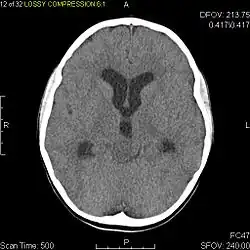

Usually – depending on the interview of the patient and after a clinical exam which includes a neurological exam and an ophthalmological exam – a CT scan and/or an MRI scan will be performed to confirm the presence of a tumor. They are usually easily distinguishable from normal brain structures using these imaging techniques. A special dye may be injected into a vein before these scans to provide contrast and make tumors easier to identify. Pilocytic astrocytomas are typically clearly visible on such scans, but it is often difficult to say based on imaging alone what type of tumor is present.